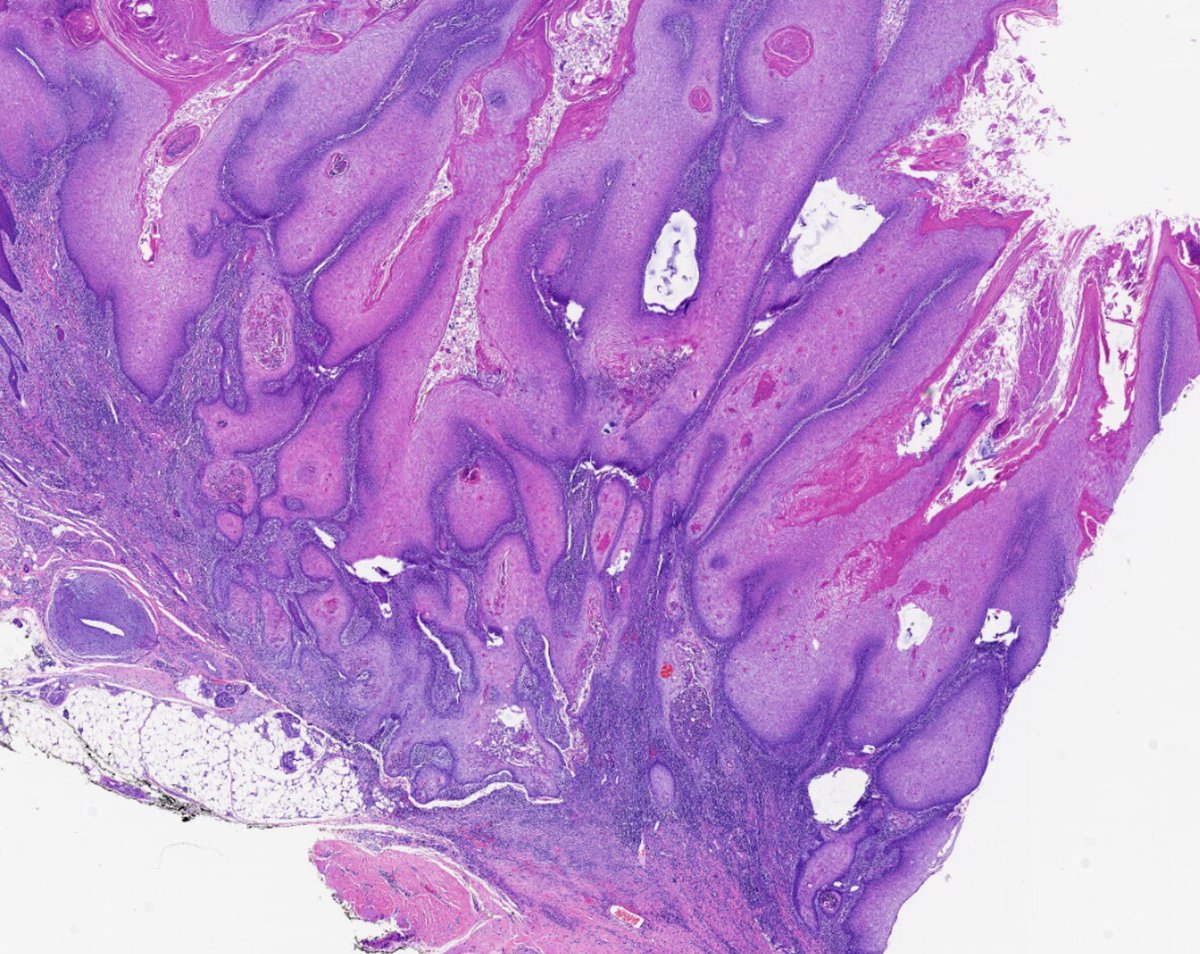

@forthejon @et565 On morphology I would have gone for HG dysplastic naevus. PRAME and molecular seem to point in the same direction here and what you have said is v reasonable. Management is the same - wider excision.

#WhatsNewInDermpath Utilizing PRAME expression and a meta-analytic framework for iSALT to explore atypical late-onset nevi of the elderly and their relationship with lentiginous and nested nevoid melanomas journals.lww.com/amjdermatopath…